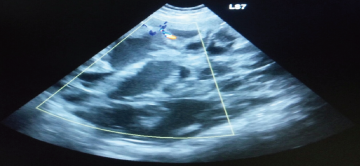

腫瘍は体の表面に出来るものが最も発見されやすく、飼い主様自身が気付き来院されることもありますが、レントゲン検査やエコー検査、血液検査などで初めて見つかる腫瘍も多数存在します。